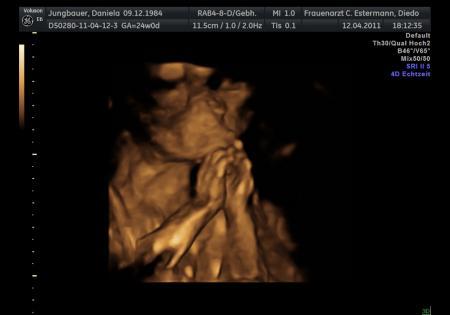

die kleine "Heilige" beim Beten!!! Des find ich ja total süß, leider ist das Gesicht voll schlecht zu erkennen und verschwommen...

Bild zu